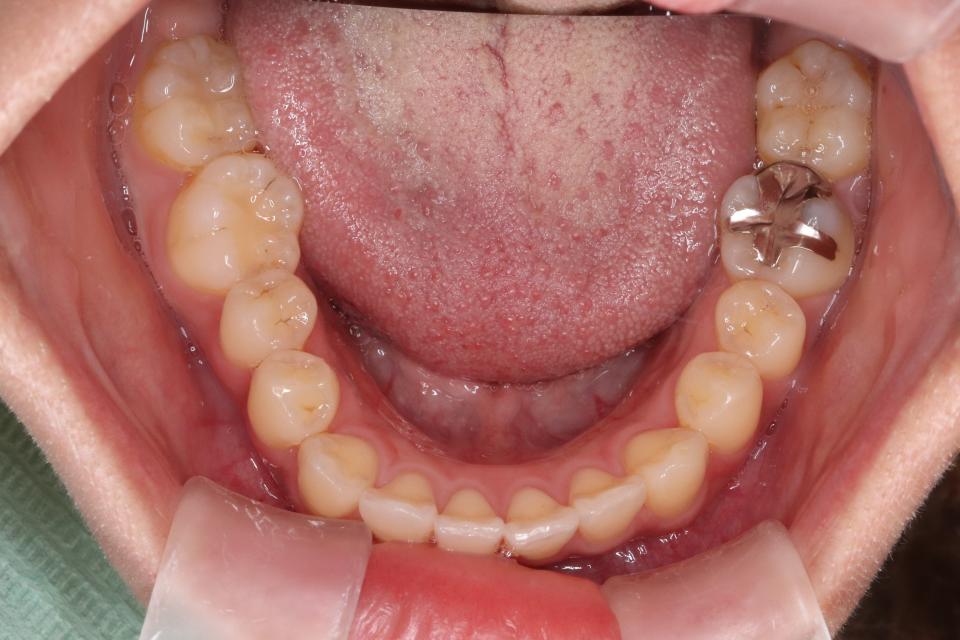

矯正治療前

希望されてましたので親知らずを4本抜歯して、歯のやすりがけ(IPR)をし、マウスピース型矯正装置(インビザライン)で矯正治療を行いました。

| 抜歯の有無 | 上下左右親知らず抜歯 |